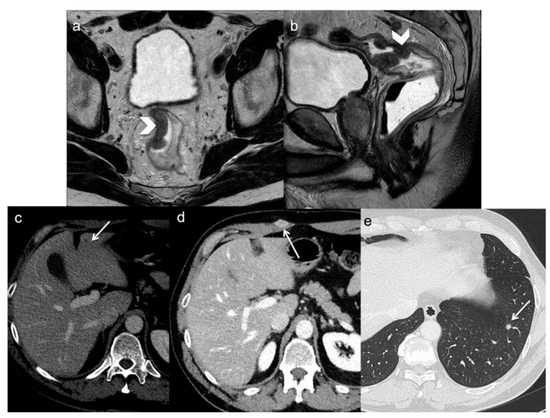

- Inoue, A.; Sheedy, S.P.; Wells, M.L.; Mileto, A.; Goenka, A.H.; Ehman, E.C.; Yalon, M.; Murthy, N.S.; Mathis, K.L.; Behm, K.T.; et al. Rectal cancer pelvic recurrence: Imaging patterns and key concepts to guide treatment planning. Abdom. Radiol. 2023, 48, 1867–1879. [Google Scholar] [CrossRef] [PubMed]

- Sinaei, M.; Swallow, C.; Milot, L.; Moghaddam, P.A.; Smith, A.; Atri, M. Patterns and Signal Intensity Characteristics of Pelvic Recurrence of Rectal Cancer at MR Imaging. Radiographics 2013, 33, E171–E187. [Google Scholar] [CrossRef]

- Dresen, R.C.; Kusters, M.; Daniels-Gooszen, A.W.; Cappendijk, V.C.; Nieuwenhuijzen, G.A.P.; Kessels, A.G.H.; Kessels, A.G.H.; de Bruïne, A.P.; Beets, G.L.; Rutten, H.J.T.; et al. Absence of tumor invasion into pelvic structures in locally recurrent rectal cancer: Prediction with preoperative MR imaging. Radiology 2010, 256, 143–150. [Google Scholar] [CrossRef]

- Messiou, C.; Chalmers, A.G.; Boyle, K.; Wilson, D.; Sagar, P. Pre-operative MR assessment of recurrent rectal cancer. Br. J. Radiol. 2008, 81, 468–473. [Google Scholar] [CrossRef]